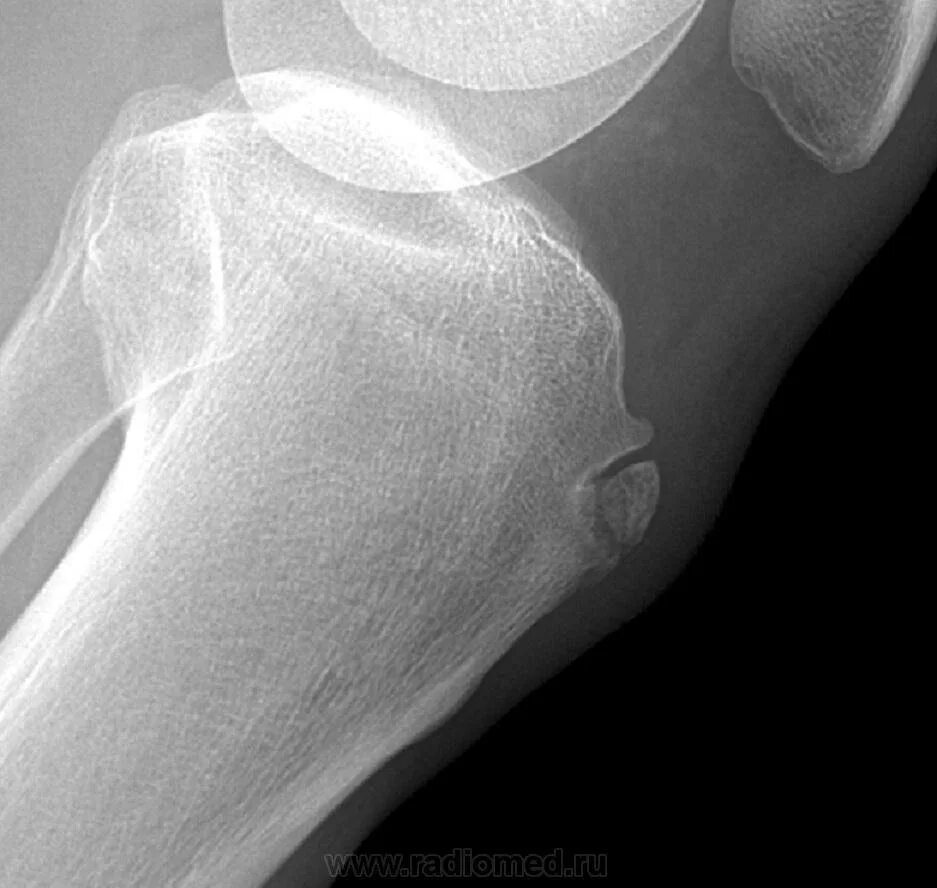

Болезнь осгут шляттера